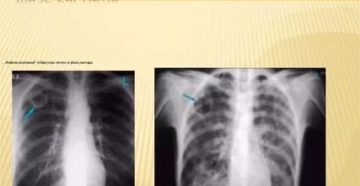

Туберкулез легких в фазе распада Быстрое прогрессирование патологии в результате поражения микобактериями приводит к разрушению…